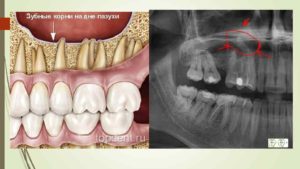

На фото: зубной корень находится в близости от дна гайморовой пазухи, что увеличивает вероятность перфорации при удалении

Такое расположение гайморовых пазух представляет опасность при стоматологических манипуляциях с верхними зубами. У каждого человека длина их корней может быть различна. У одних людей корни не доходят до дна гайморовой пазухи на 1 сантиметр, а у других пронизывают весь альвеолярный отросток и заканчиваются в полости, даже приподнимая слизистую оболочку.

Далее необходимо определить, попало ли инородное тело в полость синуса. Делать это нужно немедленно с помощью компьютерной томограммы или серии рентгеновских снимков, которые выявят степень сложности перфорации.